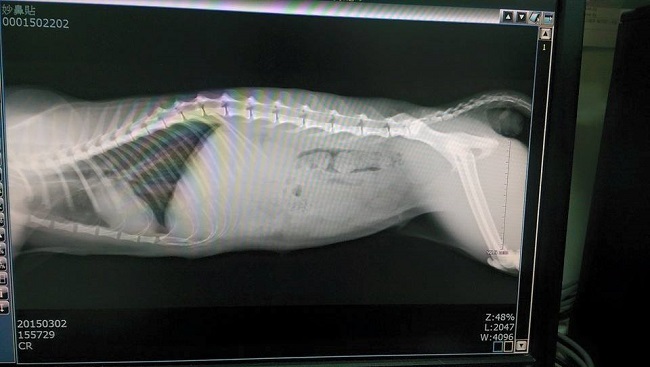

主題: 路邊發現脫肛的三花貓 申請者姓名: 簡嘉 花色: 申請日期: 2015-03-19 05:22:05 申請者部落格: 申請者臉書網址: https://www.facebook.com/catcat0528?fref=photo 所在縣市/合作醫院: 台北市/長青動物醫院 治療費用: 11286元 需求人數: 13人 已結案 (2015-04-14 17:30:16) 報名人員: Mickey(已付款)、Catbask(已付款)、莊子涵(已付款)、Riona Chiu(已付款)、Jenny wu(已付款)、李恩(已付款)、李恩(已付款)、April Tsung(已付款)、Tiffany Cheung x5(已付款)、 候補人員: 動物病情說明: 這隻三花貓(妙鼻貼)是在有天從動物醫院回程的等公車路上,意外發現的脫肛貓

醫生有提到這種通常是拉肚子.肛門太過出力導致脫肛..但因脫肛時間已超過黃金期的情況下,通常要再往內推回去有難度..但還是試試看.. 結果竟成功的推進去了..並且打抗生素消炎藥+然後有點脫水...

脫肛部位就又跑出來了,所以必須改由荷包往內縫法,並且在手術台時,確認這隻貓的骨盆較為鬆弛,醫生判斷是牠過往在生小孩生壞了...

就必須採取最後一道就是開腹腔固定結腸術or較為侵入的直腸截短...所以如果能不再脫出當然是最好,但醫生說妙鼻貼算是滿嚴重的脫肛..所以很難保證..